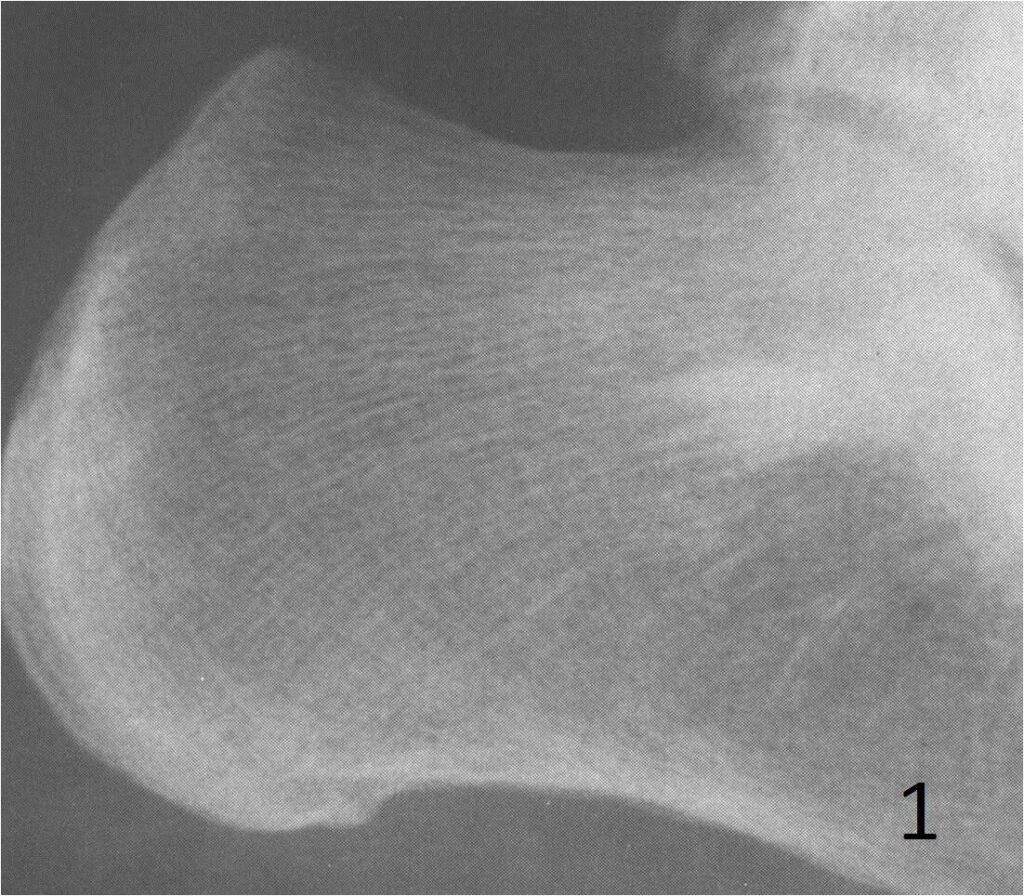

On radiographs, enostoses are round to oval and sclerotic lesions, without a periosteal reaction or bony destruction (Fig. 1). They have in the periphery of the lesion “feather-like spicules”, resembling a “brush border” making this feature useful to recognize them. The spicules at the periphery blend in with the surrounding bony trabeculae. CT shows a blastic lesion, without periosteal reaction with radiating spicules at the periphery. The spicules may be more discernible on a CT scan than on plain x-ray (Fig. 2). MRI, shows no bone disruption or bony destruction, and is hypointense on both T1 and T2 weighted MR images. Bone islands are inert on bone scans, except when they are large. They may be quite active and hence may be worrisome for a malignancy.

Fig. 1: Lateral plain Xray of calcaneous shows a bone island near the subtalar joint. The bone island appears as a sclerotic and spiculated lesion. This lesion was found incidentally during an evaluation for a sprained ankle.